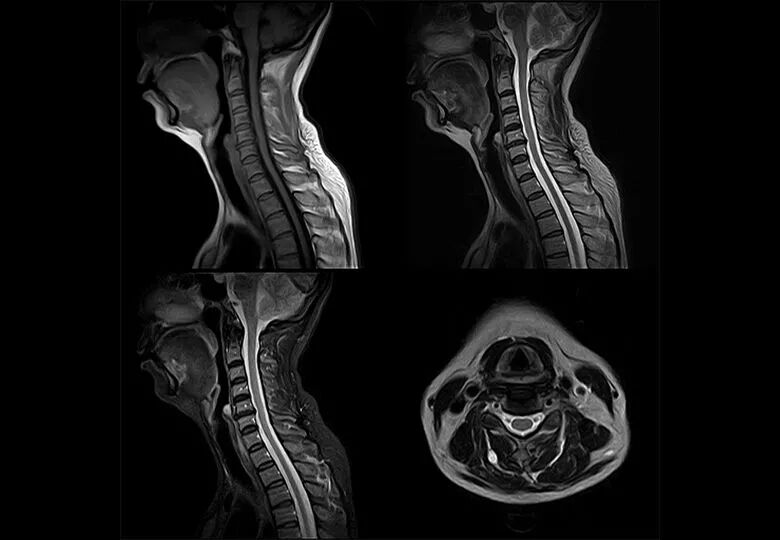

磁共振图像举例

dr在彩超什么意思一文搞懂X线、CT、MR、彩超检查的区别_https://www.jmylbn.com_新闻资讯_第16张

骨骼和钙化的地方水最少,所以如果你骨折了,说要拍个X线片是可以的,做个CT检查也可以。但要是做核磁共振扫描,那我劝你还是别做了,因为核磁共振看不清楚。但是,骨骼边上的那些肌肉,关节的软组织、韧带等本来CT检査是看不清楚的,核磁共振扫描却一览无遗。肌肉拉伤了,核磁共振能分辨哪根肌腱受损,损伤到什么程度。

除了肌肉、韧带含水较多以外,脑的含水量也很大,所以脑部做核磁扫描也非常清楚。

颈椎腰椎:最佳选核磁,次选CT